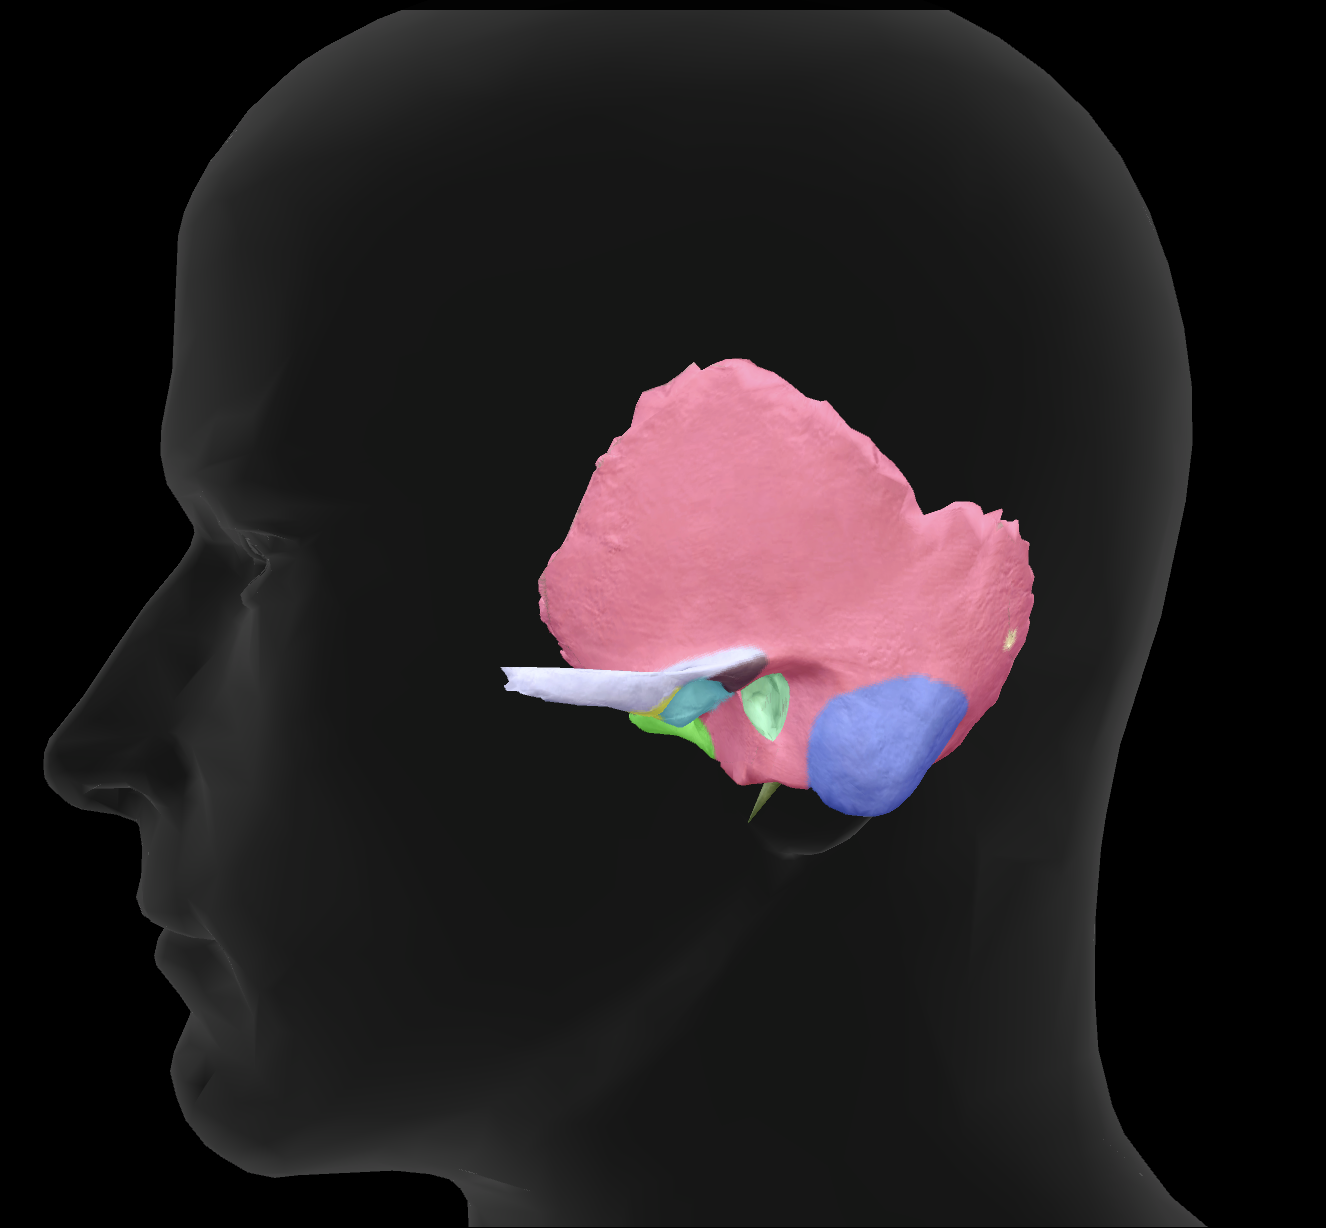

What bone is highlighted?

zygomatic bone

zygomatic process of temporal bone

What is the name of this feature?

external auditory meatus

What is the name of this feature?

mandibular fossa

What is the name of this feature?

mastoid process

What is the name of this feature?

styloid process

What connects to the zygomatic process to make the zygomatic arch?

temporal process of the zygomatic bone